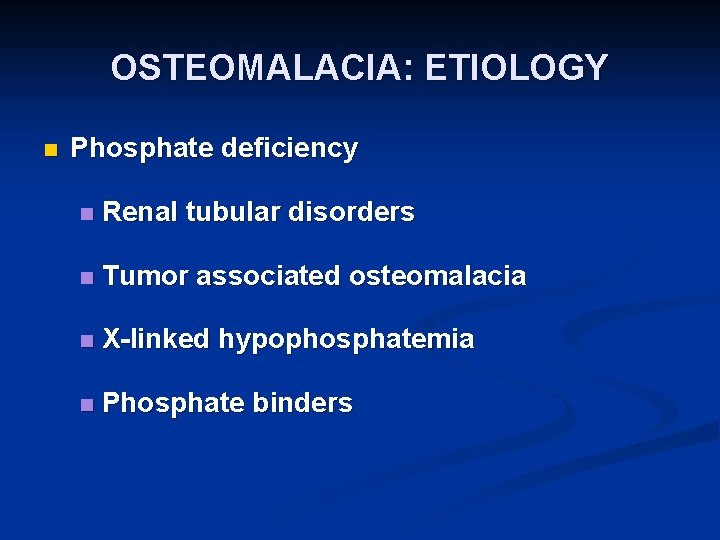

OSTEOMALACIA: ETIOLOGY n Phosphate deficiency n Renal tubular disorders n Tumor associated osteomalacia n X-linked hypophosphatemia n Phosphate binders